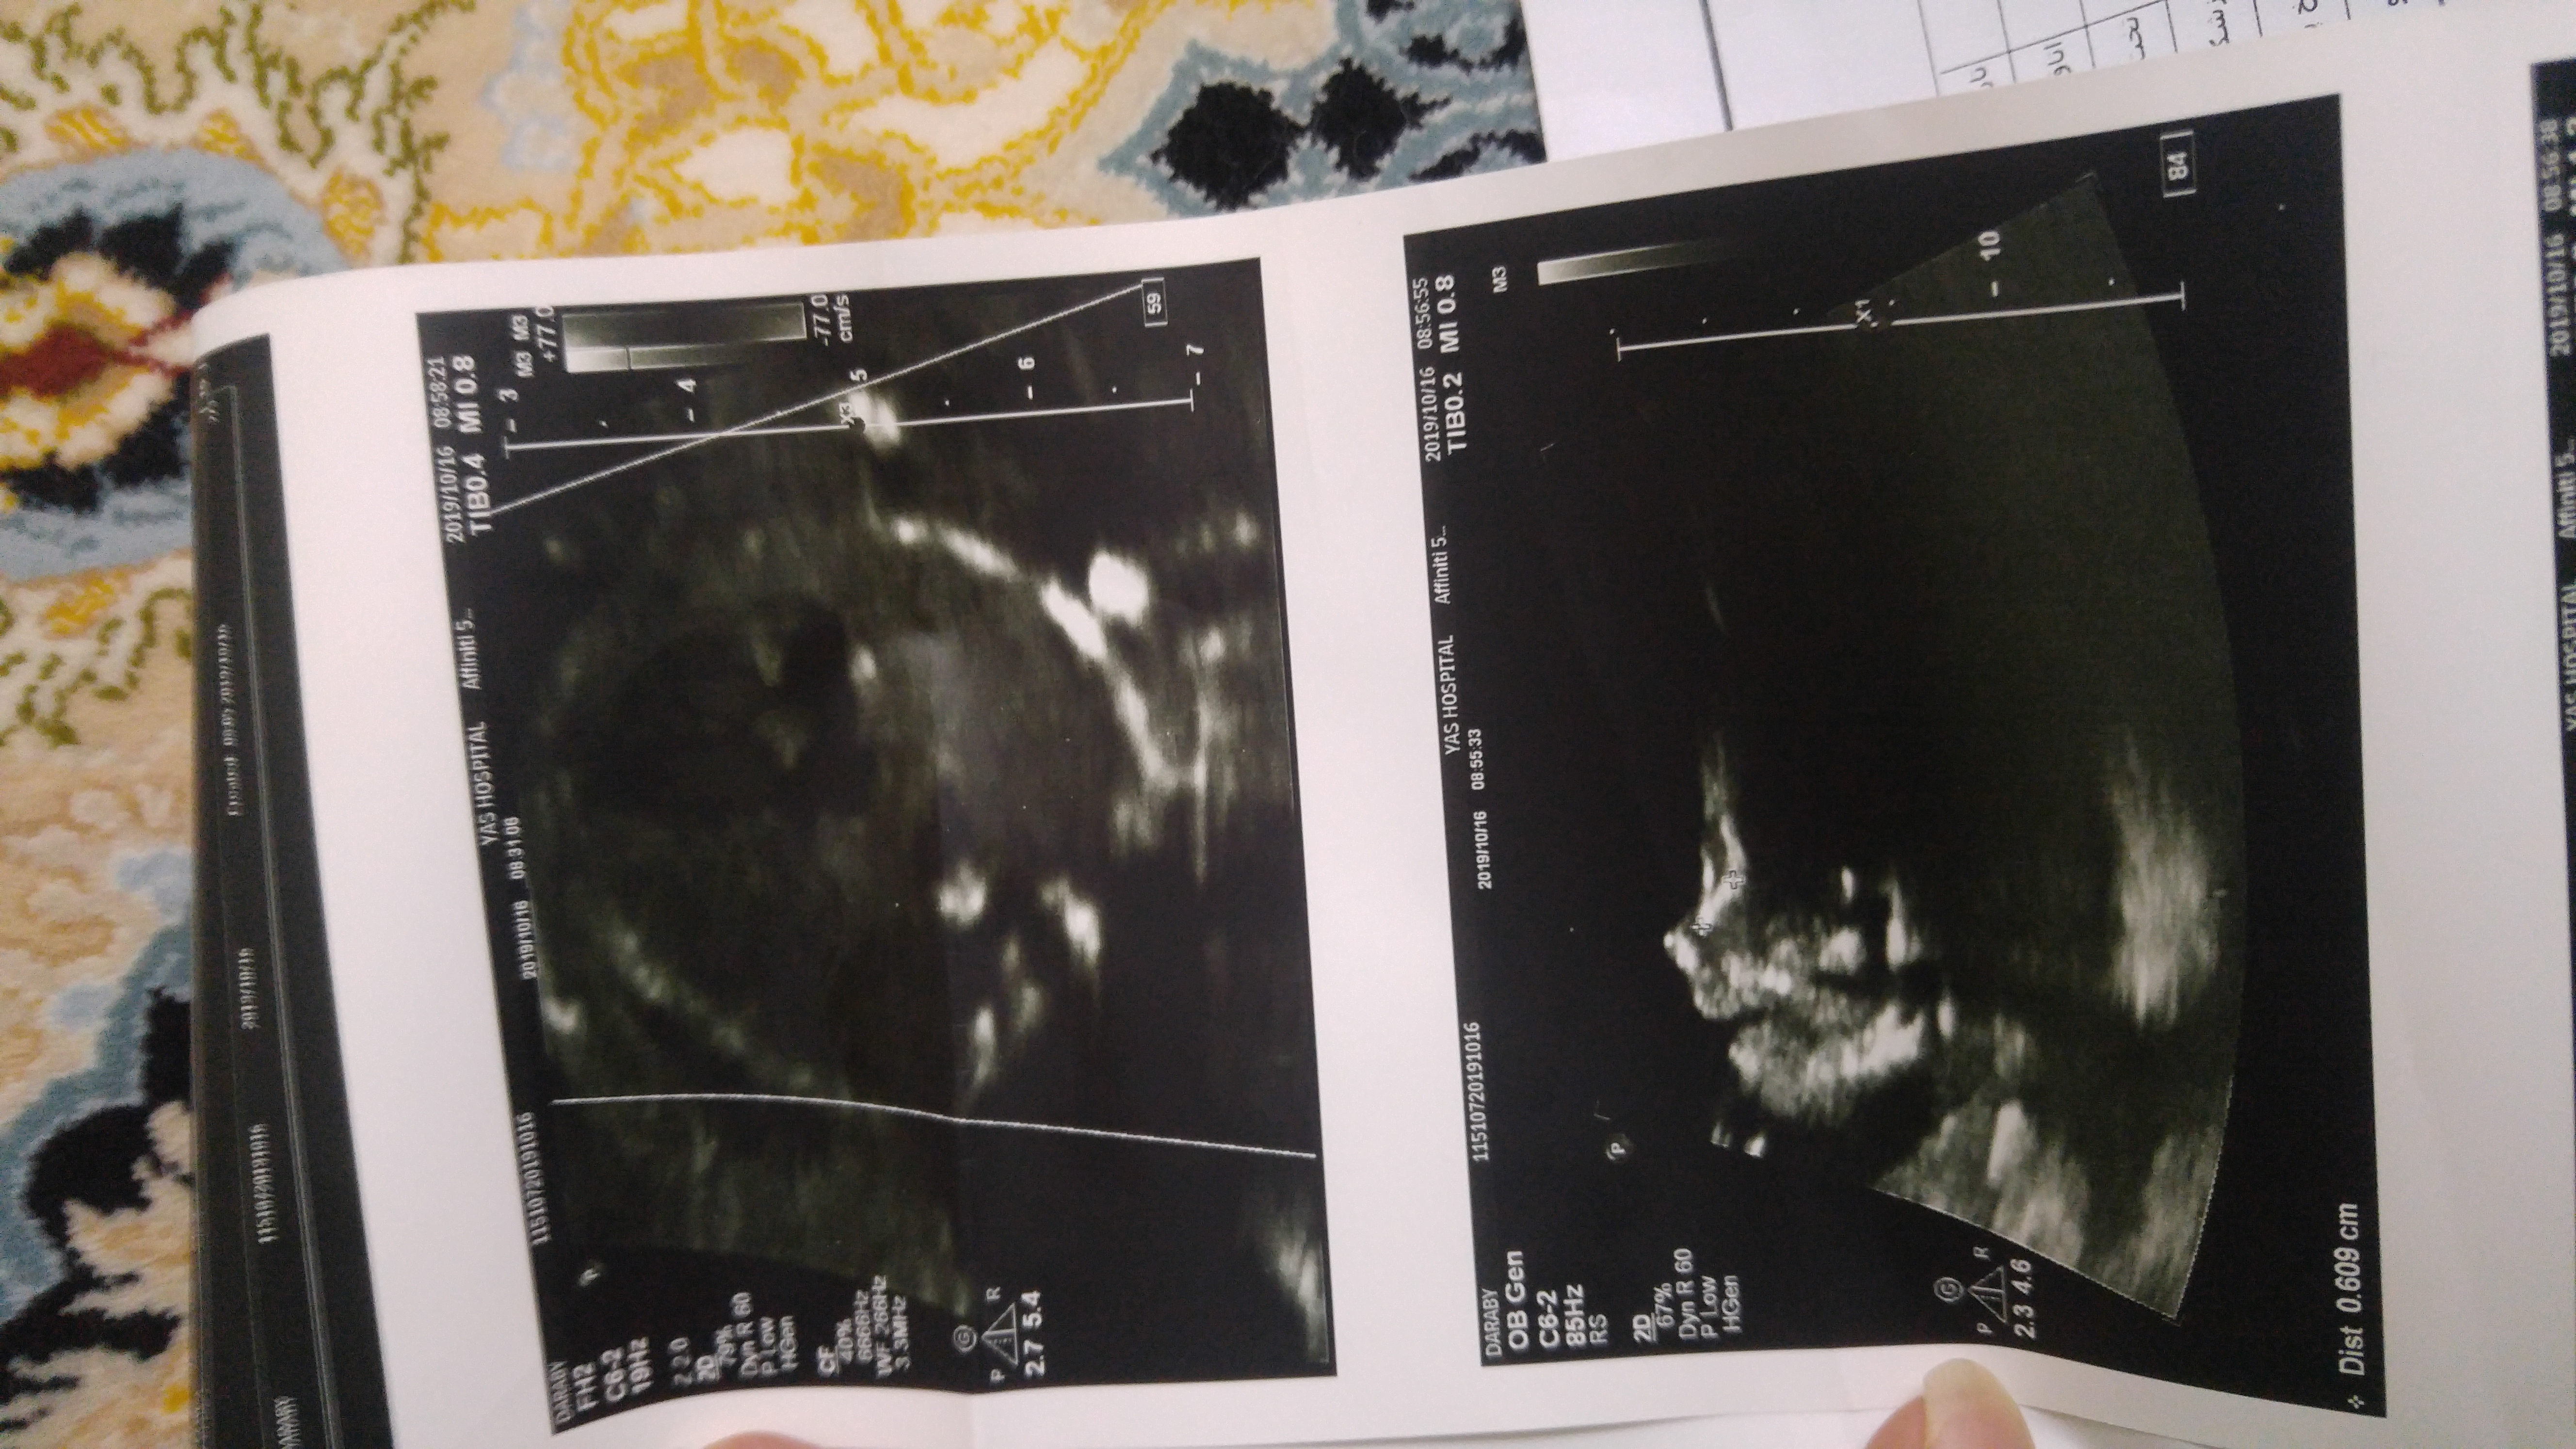

هفته 20 ...4 روز پیش رفتم سونو

نه اصلا عکس واضح ندارم ازش....چندتا دادن نمیدونم چی به چیه

اینابودن نمیدونم اوکی هست یا نه